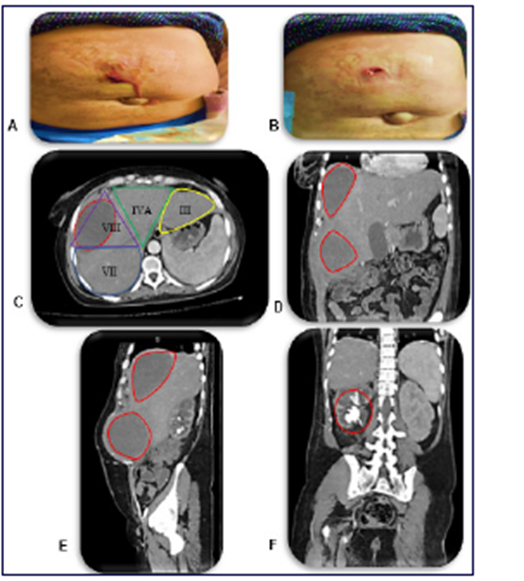

Paciente femenino de 38 años con diagnóstico de Litiasis renal derecha coraliforme complicado con hidronefrosis grado III hace 6 meses que ameritó inserción de catéter doble j, acude por presentar salida de secreción purulenta a través de pared abdominal de 7 días de evolución. Posteriormente se asocia dolor abdominal de aparición súbita, en cuadrante superior derecho, de moderada intensidad. Al examen físico, hemodinámicamente estable. Abdomen, globoso a expensas de panículo adiposo, blando, deprimible, doloroso a la palpación profunda en hemiabdomen derecho, donde se palpa masa de bordes regulares redondeada, renitente de 15x18 cm de diámetro que se extiende desde hipocondrio derecho a epigastrio donde se observa perdida de solución de continuidad de 2 cm, con salida de exudado purulento de 200cc. (Figura 1A-B).

Los laboratorios reportaron hemoglobina 6,3 gr/dl y hematocrito en 22%. Se evidenció tomografía de abdomen y pelvis contrastada donde se observa absceso hepático en segmento VIII de 10x5,9x8 cm con volumen de 250cc, (figura 1C), absceso en planos de pared abdominal anterior de 13x7,9 cm de diámetro con volumen de 650cc, (Figura 1D-E), cálculo coraliforme en riñón derecho, (Figura 1F), con catéter doble j normoinserto.

Figura 1 Examen fisico de pared abdominal. A. Salida de exudado purulento a través de pared abdominal. B. Se evidencia perdida de solución de continuidad de 2 cm en epigastrio. C. Corte axial de tomografía de abdomen y pelvis contrastada, donde se observa (Linea roja) absceso hepático en segmento hepático VIII con medidas de 10 x 5,9 x 8 cm con un volumen promedio de 250cc y su relacion con la segmentaciòn hepática, representada por lineas de colores: Azul (VII), Morado (VIII), Verde (IV A), Amarillo (III). D. Corte Coronal de tomografía de abdomen y pelvis contrastada, donde se observa (Lineas rojas) abscesos (Superior, hepático) e (Inferior, pared abdominal anterior). E. Corte Sagital de tomografía de abdomen y pelvis contrastada, donde se observa (Lineas rojas) abscesos (Superior, hepático) e (Inferior, pared abdominal anterior). F. Corte Coronal de tomografía de abdomen y pelvis contrastada, donde se observa (Linea roja) riñón derecho con litiasis coraliforme.